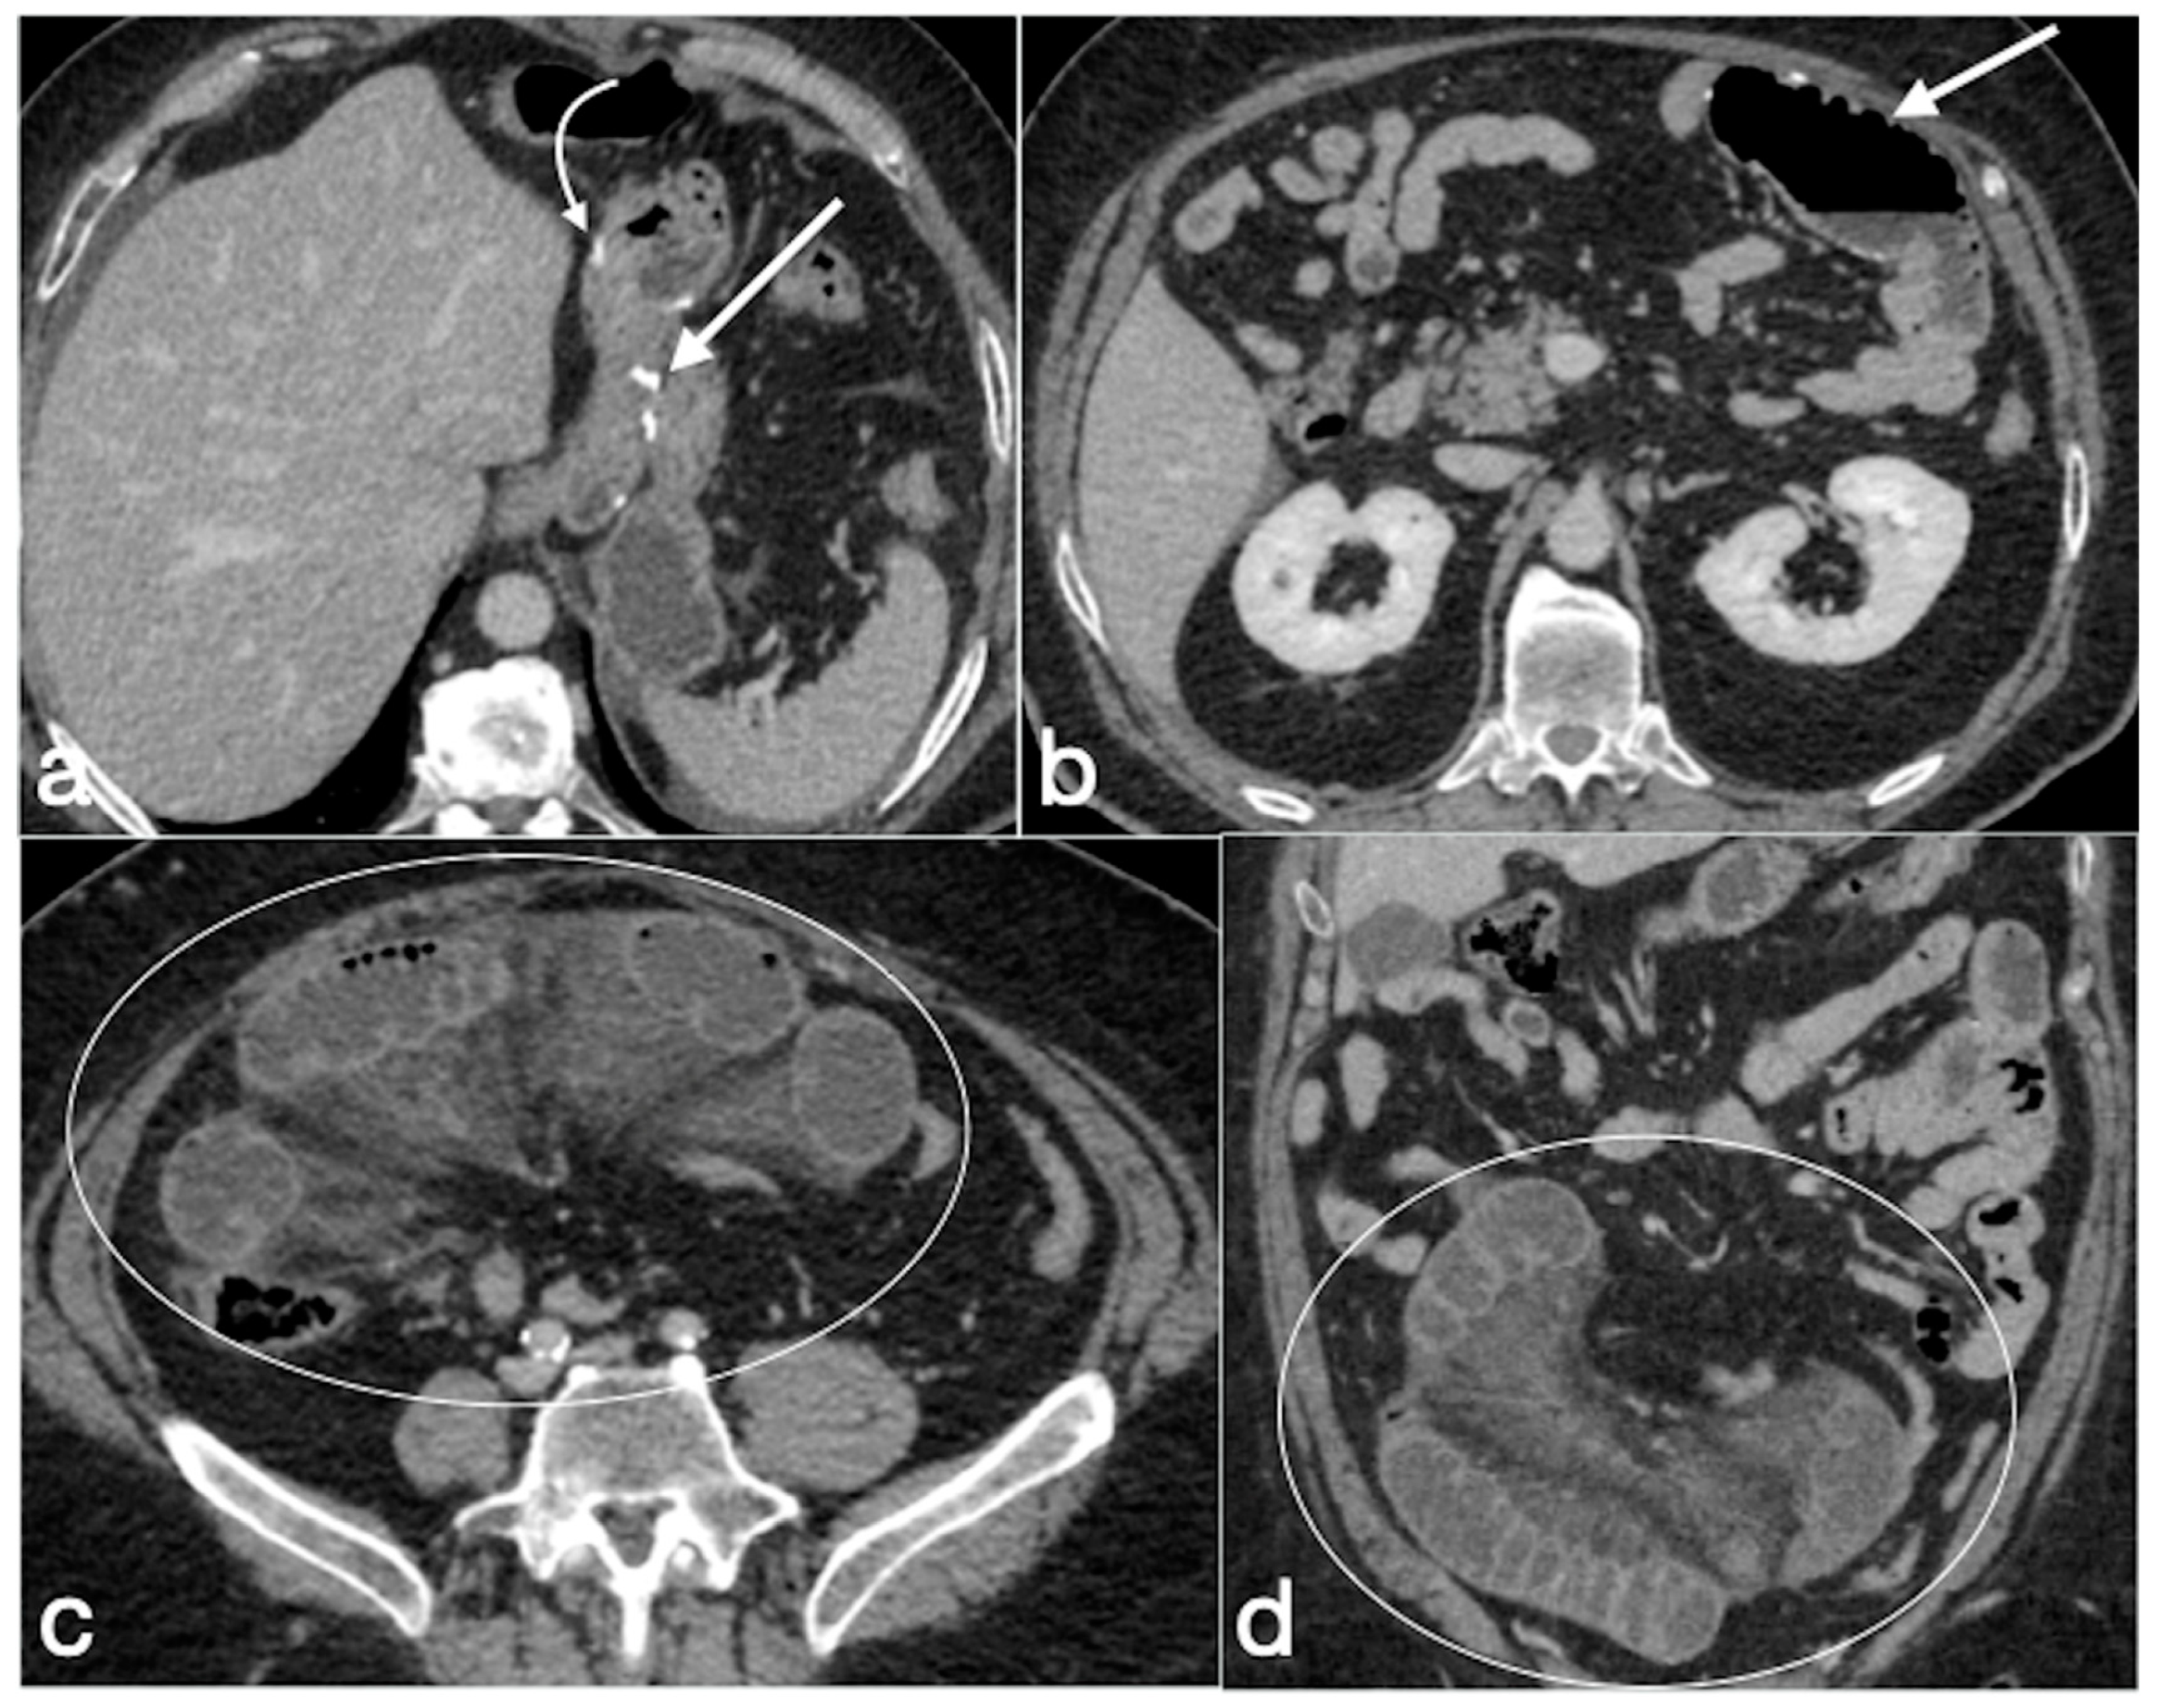

Figure 19. Patient 1. Porto-spleno-mesenteric venous thrombosis and colonic ischemia after sleeve gastrectomy. A 37-year-old female patient underwent sleeve gastrectomy. The patient came to the emergency department complaining of abdominal pain and fever. See the surgical gastric suture (a, coronal oblique view), the enlarged and thrombosed spleno-portal lumen (b, axial view; c, coronal oblique view, straight arrows), the consequential mesenteric congestion (d, axial view; e, coronal view, curved arrows), and the colonic ischemia (d, axial view; e, coronal view, circles). In the coronal view (e), the thrombosis that extends to the superior mesenteric vein lumen can be seen best. The patient was treated with multiple session of transhepatic catheter-directed thrombolysis.